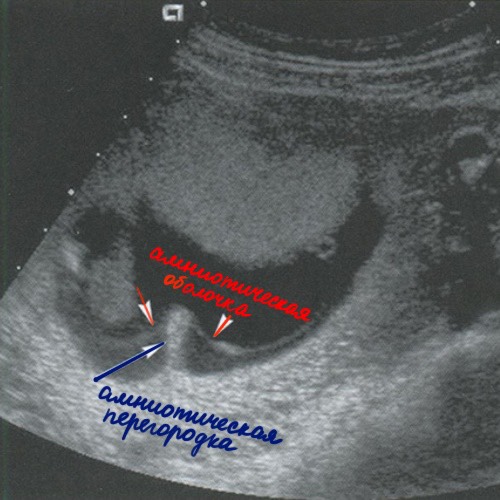

Если имплантация произошла на участке эндометрия с маточной синехией, тогда в процессе роста и развития амниотическая и хориальная оболочки подтягиваются к центру плодного яйца. А затем в полости плодного яйца (пузыря) образуется амниотическая перегородка, которая состоит из 4 слоев: двух слоев амниотической оболочки и двух слоев хориальной оболочки.

Амниотическая перегородка никогда не разделяет плодный пузырь на две части, хоть на УЗИ в определенных срезах может так показаться. И самое главное, амниотическая перегородка в отличие от амниотических тяжей никогда не прикрепляется к плоду, а значит не приносит ему никакого вреда. Иногда даже плацента может лежать на этой перегородке.